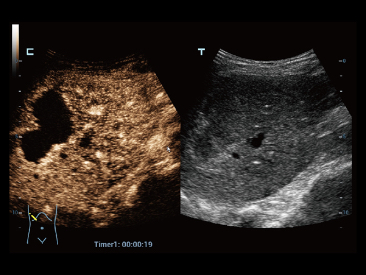

Die St?rken des Resona 7 sind bis ins kleinste Detail durchdacht. Seine erstklassige Bildqualit?t ist das Ergebnis einer erfolgreichen Fusion. Mindray und Zonare Medical Systems haben ihren Kernkompetenzen geb├╝ndelt, um ein Premiumsystem Wirklichkeit werden zu lassen. Dank der Vector Flow-Funktion k?nnen bei Gef??untersuchungen mehr als 400 Bilder pro Sekunde dargestellt werden. Somit entstehen ganz neue M?glichkeiten der Diagnose.

Dank der ZONE Sonography?-Technologie (ZST+) wird das B-Bild des Resona 7 ├╝ber die komplette Tiefe fokussiert, sodass keine Fokuspunkte mehr gesetzt werden m├╝ssen. Die Schall-Lauf-Geschwindigkeit (SSC) wird auf Knopfdruck individuell auf den Patienten angepasst, was die Darstellung von Organen, Grenzfl?chen und Gewebever?nderungen erheblich verbessert. Und dank der fortschrittlichen iFusion-Funktion k?nnen optional die Daten von Ultraschall-, MRT-und CT-Bildern synchronisiert werden.